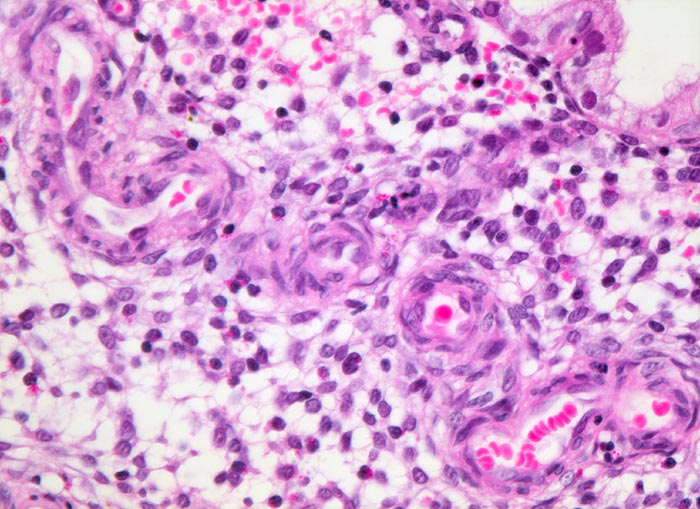

Endometrium in Sekretionsphase: Spiralarterien

Ödematöses Stroma mit prominenten gewundenen Spiralarterien. Das angrenzende Stroma ist ödematös. Es enthält Körnchenzellen mit rotem Zytoplasma. Das Epithel der endometranen Drüsen ist einreihig.